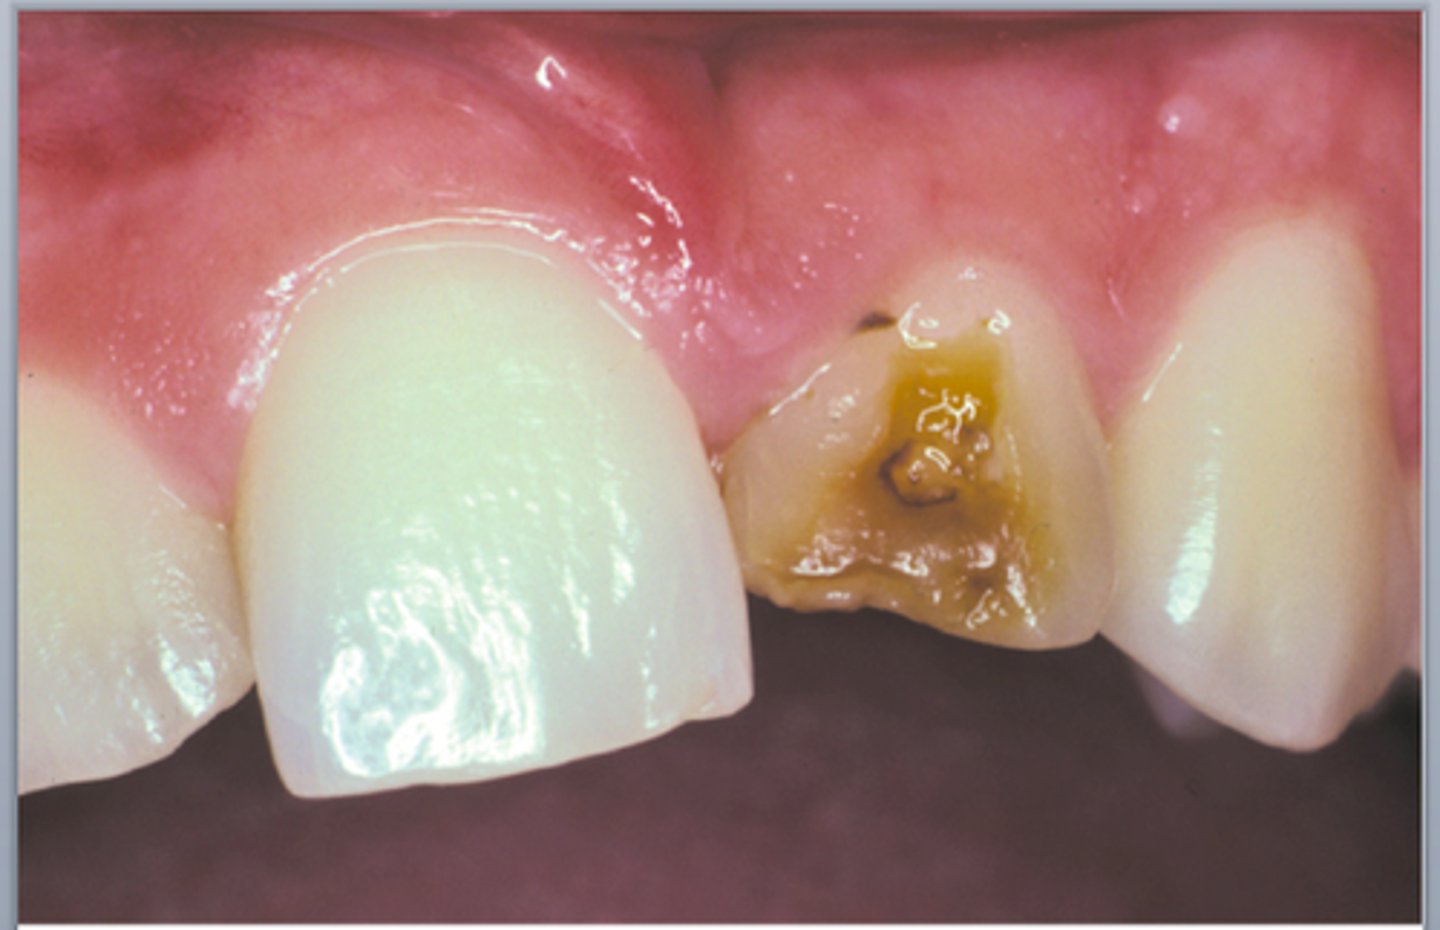

Amelogenesis imperfecta Xray

(Look up other examples too) Amelogenesis imperfect is a disorder of tooth development - causes teeth to be unusually small, discolored, pitted or grooved, and prone to rapid wear and breakage